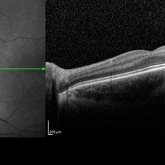

OCT/infrared image showing myopic fundus with normal retinal structure in patient with CACNA1F associated X-linked CSNB (OS).

Photographer: Jing Zhang, Ophthalmic Photographer

Condition/keywords: congenital stationary night blindness (CSNB), infrared image, optical coherence tomography (OCT)